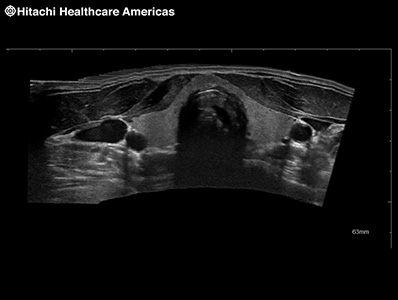

Trapezoidal display on linear transducers provides a wider diagnostic field of view.

Provides an extended field-of-view image created from a series of real-time images. As the user moves the transducer across the area of interest a larger image is created that provides clearer spatial relationship information of anatomy and structures. This is especially helpful in assessing structures that are larger than the transducer field of view.